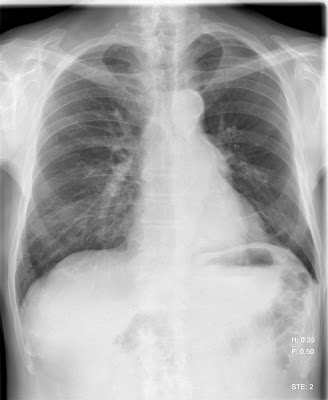

Hirtelen kezdődött mellkasi fájdalom a bal oldalon. Az előzményben korábbi PTX, bullák nincsenek.